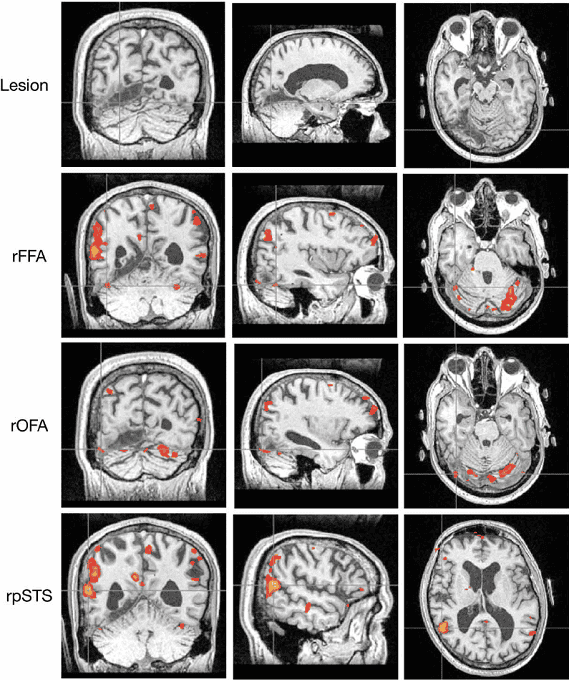

Se trata de una enfermedad neurológica llamada prosopagnosia, también conocida como "la ceguera de rostros", y se define como una forma de agnosia (incapacidad de procesar información sensorial) visual. Este trastorno no solo se caracteriza por provocar la incapacidad de reconocer caras de familiares o personas conocidas, sino incluso el rostro de uno mismo. Su singularidad radica en que aunque la persona que lo padece puede reconocer las diferentes partes de un rostro, no puede unificar esa información y procesarla como un conjunto. Alguien con este padecimiento puede no reconocerse a sí mismo, incluso aunque esté viéndose en el espejo o en una fotografía. Actualmente, se sabe que existen dos tipos de prosopagnosia: la congénita y la adquirida. La congénita (o del desarrollo) viene desde el nacimiento, y se debe a una interrupción en la comunicación entre diferentes partes del cerebro, por lo que el individuo no desarrolla adecuadamente la capacidad de reconocer rostros. Es padecida por el 2,5% de la población. La adquirida, en tanto, se debe al daño en el lóbulo temporal occipital provocado por accidentes cerebrovasculares, hemorragias o tumores, entre otras causas. Se encuentra con mayor frecuencia en adultos. Aunque no existe ninguna cura para esta afección, mucha gente que la padece tiende a enfocarse en características particulares de la persona para poder reconocerla, como una cicatriz, la forma de vestir o el tono de la voz.